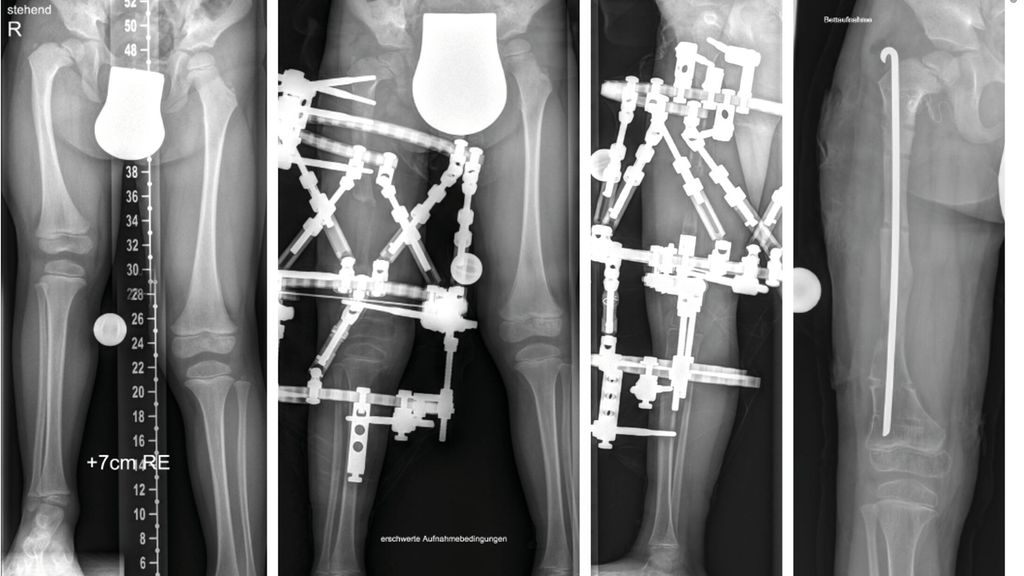

Sowohl beim CFD wie auch bei der FH zeigen sich deutliche Pathologien am Kniegelenk. Es besteht eine Hypoplasie der lateralen Epiphyse mit entsprechenden Wachstumsstörungen, was zu einem rezidivierenden Valgus am Kniegelenk führt.3,4 Zusätzlich besteht in vielen Fällen eine deutliche Instabilität des Kniegelenkes. Es findet sich eine Hypoplasie des ACL in etwa 15% und ein vollständiges Fehlen des ACL in etwa 85% der Fälle.5 Das PCL ist in etwa 21% hypoplastisch und in etwa 24% ebenso fehlend. Diese Instabilität des Kniegelenkes ist bei milden Formen oft klinisch im Alltag nicht relevant, kann jedoch während einer Verlängerung zu massiven Problemen im Sinne von Luxation und Subluxation führen. Zusätzlich zeigt sich oft eine Lateralisation der Patella, wobei diese auch permanent luxiert lateral am Femurkondyl liegen kann.

Die Valgusstellung kann sehr einfach über eine Wachstumslenkung (Hemiepiphysiodese mit 2-Loch-Platte) korrigiert werden. Um eine Subluxation am Kniegelenk zu verhindern, muss bei allen diesen Fällen bei Verlängerung mit Fixateur dieser knieüberbrückend montiert werden (Abb.4). Bei Verlängerung über einen Verlängerungsmarknagel wird in diesen Fällen eine Oberunterschenkelschiene (KAFO) verwendet und prophylaktisch, soweit noch vorhanden, die Fascia lata auf Höhe des oberen Patellapols durchtrennt. Bei deutlicher Instabilität oder auch Subluxation ist eine Stabilisierung über eine komplexe Operation, die als Super-Knee-Operation subsumiert wird, erforderlich.2 Diese Operation kann auch an die Hüftrekonstruktion/Super-Hip-Operation angeschlossen werden, da hier die Faszie ohnehin präpariert wird. Je nach Alter des Patienten und dem Ausmaß der Instabilität wird hierbei die Fascia lata nach Präparation bis an das Tuberculum Gerdyi und Halbieren der Länge nach entweder extraartikulär oder intraartikulär geführt. Auch die Fixation wird abhängig vom Alter mit Biotenodeseschrauben oder Weichteilzügelung durchgeführt.

Abb. 4: Platzierung (a–d) eines Fixateur externe mit Knie-Überbau (e–g) zum Schutz vor (Sub-)Luxation